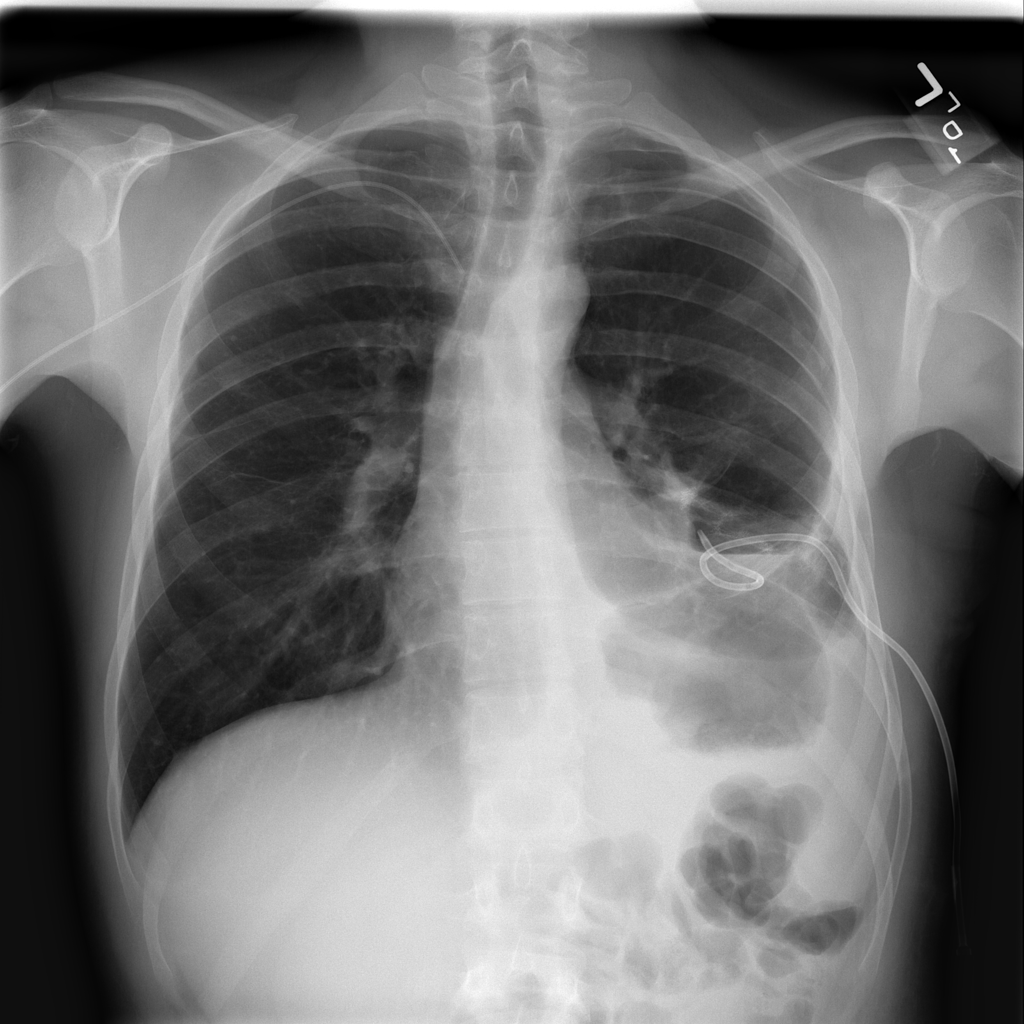

PAT-4639 · IMG-013Pneumothorax

PAT-4639 · IMG-013

AP